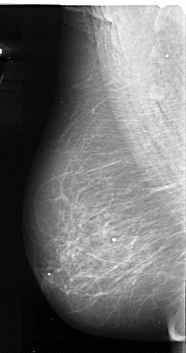

A_1085_1.RIGHT_MLO

A_1085_1.RIGHT_CC

RIGHT_CC LINES 5581 PIXELS_PER_LINE 2806 BITS_PER_PIXEL 16 RESOLUTION 42 OVERLAY

RIGHT_MLO LINES 6286 PIXELS_PER_LINE 3001 BITS_PER_PIXEL 16 RESOLUTION 42 OVERLAY